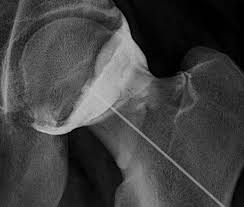

2) l'introduction de l'aiguille

3) la vérification du bon placement de l'aiguille par une ponction de liquide et/ou une injection de produit iodé (en dehors de tout problème allergique)

4) l'injection du produit.